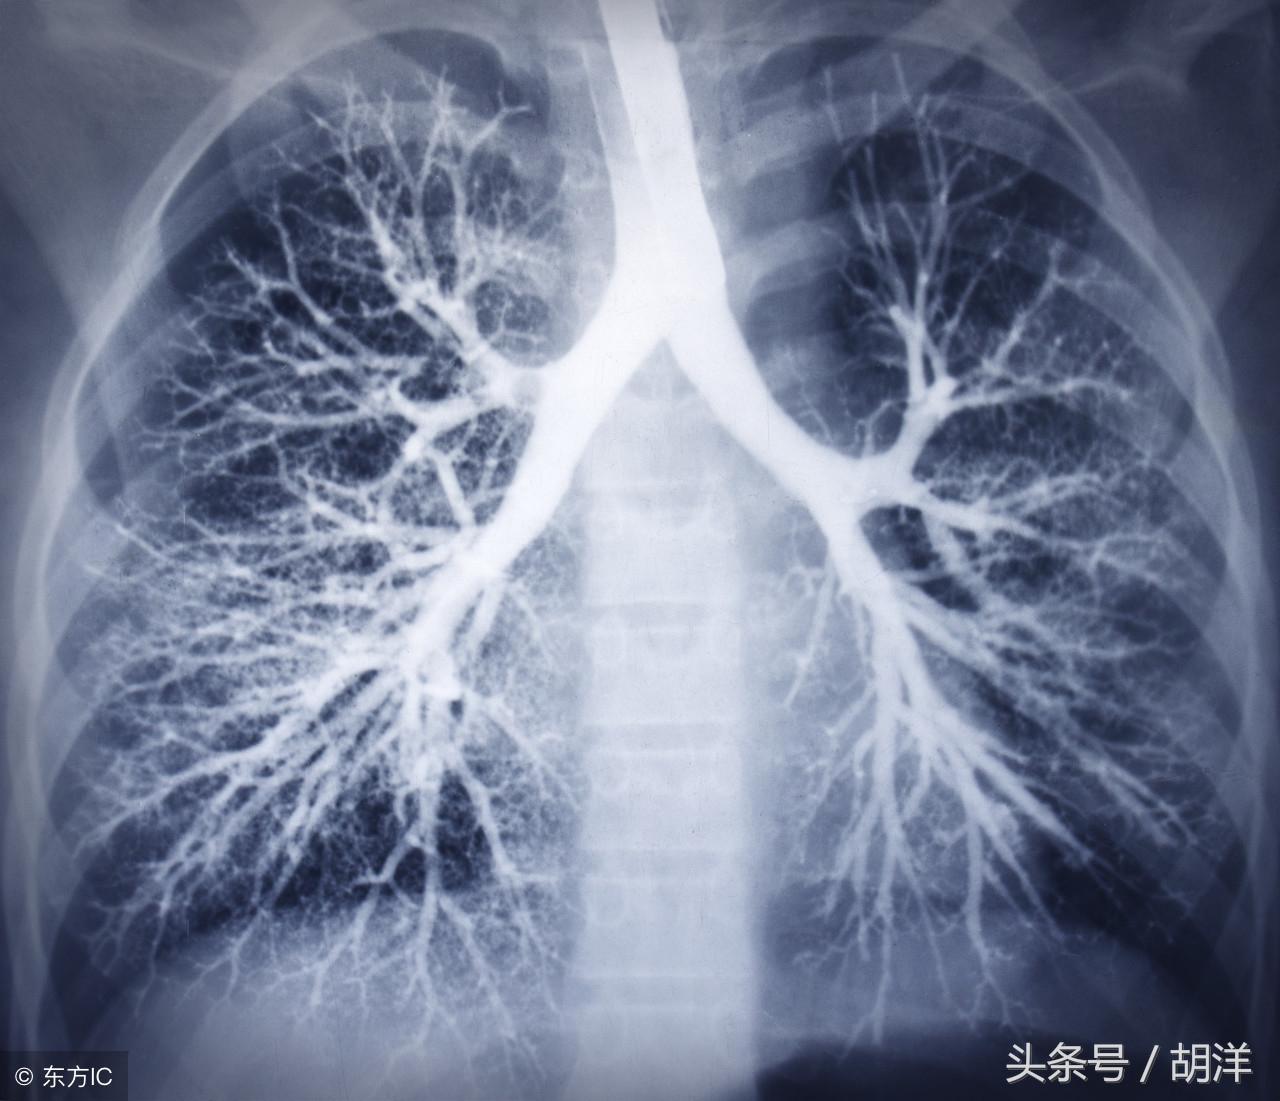

咳血又称咯血,是呼吸科一个比较严重的症状,由于其可能提示肺部肿瘤等严重疾病而受到重视,但事实上在引起咯血的病因中,肺部恶性肿瘤所占的比例并不是很大,但很多人因咯血而焦虑异常,特别是咯血久治不愈情况下,更加令人无法正常的生活和学习,那么哪些疾病可能导致反复发作痰中带血或者咳出满口鲜血呢?

支气管扩张是一种支气管管壁结构破坏性疾病,正常情况下,支气管是一个带有弹性,拥有一定管径的能够维持正常呼吸通气的结构,当管壁结构受到破坏时,气管会受到被动的牵拉而扩张,管壁的血管由于弹性较小,容易被撕扯呈血管瘤改变,一旦胸腔内血流压力增大可能冲破血管瘤变薄的管壁而导致大咯血,少量渗血时则呈现为痰中带血。

曲霉菌是一种常见的真菌,正常情况下,曲菌很少感染肺部结构正常,免疫力良好的人群,当肺部受到破坏,特别是形成较大空洞和支气管扩张时,曲霉菌可以趁机进入空洞扩张的支气管内与其中渗出的白细胞、纤维素等成分形成球状结构,成为曲菌球,曲菌球在空洞内能够自由的活动,对空洞壁有机械性的损伤,当损伤到管壁变异的血管瘤时,极有可能导致大出血。